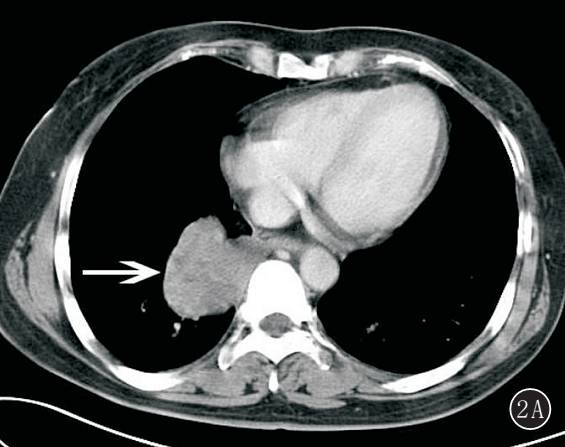

图 3A,B 右上肺滑膜肉瘤。 A. 增强后肿块边缘可见强化的包膜,内部见低密度坏死区,肿块与邻近的胸膜组织粘连,伴右侧胸腔积液;B. 梭形细胞相对较小,细胞密度较高,较一致,核染色细腻(HE ×100)